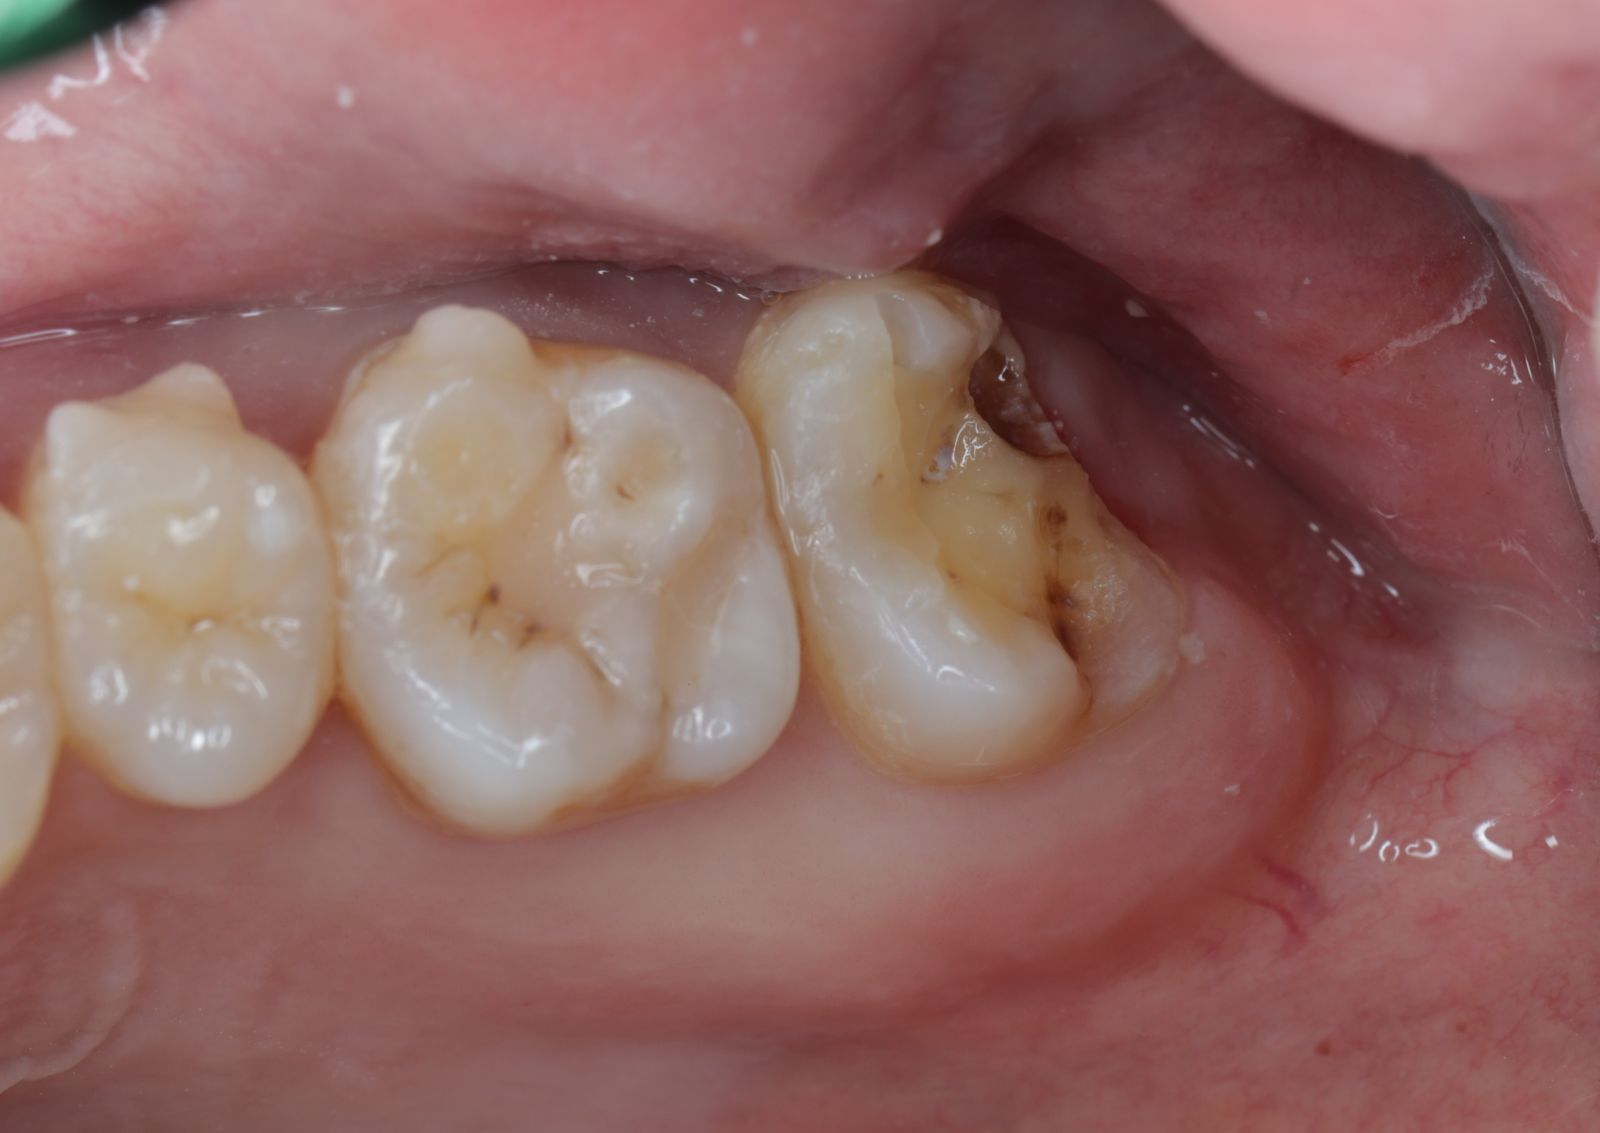

【 案 例 三】

- 有時候表面上看起來是蛀牙是一個小缺口,其實裡面已經是範圍很大的蛀牙了!用隔濕的小帳棚隔絕汙染、清理蛀牙,缺損的齒質就靠陶瓷齒雕(瓷塊)做修復!仿真的色澤及外觀,讓你看不出來牙齒曾經的損傷。